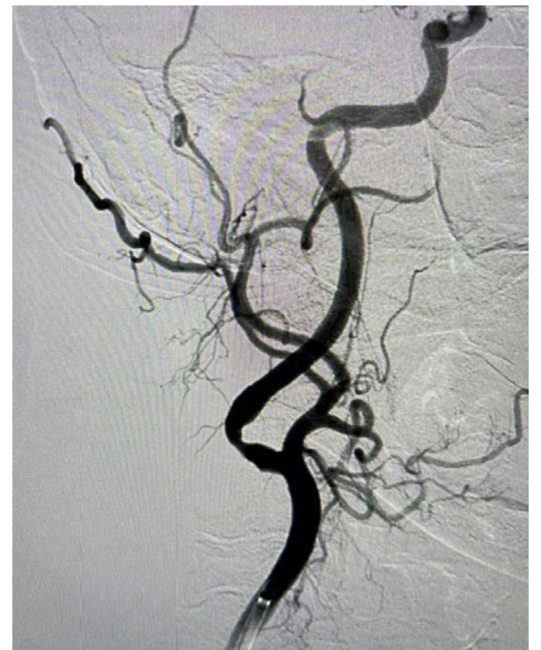

The patient underwent elective carotid stenting as a staged procedure prior to transcatheter aortic valve replacement (TAVR). Her previous diagnostic study utilized right radial artery access but it was difficult to perform selective carotid angiography, specifically that of the left carotid artery.5 Consequently, this intervention was performed from the right groin. A VTK catheter (Cook Medical) was placed in the right common carotid artery, followed by a TAD guidewire (Abbott Vascular) and then a Flexor Shuttle sheath (Cook Medical) with no difficulty. There was no difficulty deploying a large filter wire (NAV RX 7.2 mm, Abbott Vascular), and we were able to dilate with a 4-mm x 15-mm balloon (Abbott Vascular). However, we could not pass a 6/8 self-expanding stent (Abbott) (Figure 1). We performed further predilation with a 6-mm x 15-mm balloon, but we were still not able to pass the 6/8 stent. Because we had already performed adequate predilation, we attempted to pass a 2-cm self-expanding stent (Abbott Vascular) but were still unable to cross the lesion. Finally, we performed predilation balloon angioplasty with a 7-mm x 15-mm balloon (Abbott Vascular), which ultimately allowed us to pass the 6/8 self-expanding stent. After deployment, we removed the filter and a subsequent arteriogram confirmed that the lesion had completely resolved (Figure 2). The patient had no hypotension or bradycardia during the procedure and was discharged the following day. She will undergo TAVR at a later date. This case exemplifies using stepwise predilation of a severely calcified carotid lesion, demonstrating an option for operators.